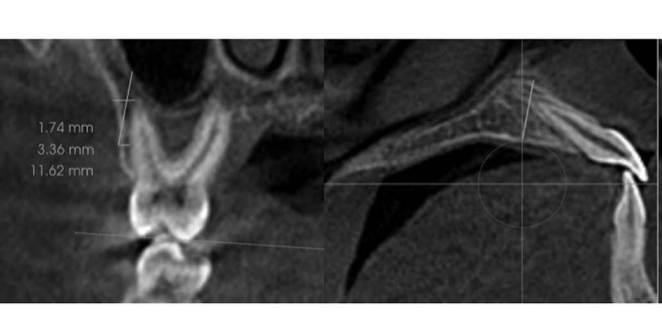

Neste estudo retrospectivo com tomografia computadorizada de feixe cônico, 162 indivíduos (81 homens e 81 mulheres, idade média de 16,05 ± 0,65 anos) foram avaliados. Eles foram divididos em três grupos (hipodivergente, normodivergente e hiperdivergente) com base no ângulo do plano mandibular de Frankfurt. Dez medidas ósseas vestibulares foram feitas em duas secções coronais diferentes: raízes mesiovestibulares do primeiro molar superior e raízes distovestibulares (bilateralmente). Seis medidas do osso palatino foram feitas em um corte sagital nos incisivos centrais superiores (bilateralmente). Um total de 32 medidas por pacientes foram consideradas no estudo.

Nenhuma diferença significativa foi observada para o IZC (largura e ângulo) na raiz mesiovestibular do primeiro molar superior. Uma comparação dos grupos normodivergentes e hiperdivergentes para a largura vestibular na raiz distovestibular do primeiro molar mostrou diferenças significativas. A espessura do osso palatino no nível de 2 mm distal ao ápice do incisivo central foi significativamente maior no grupo hiperdivergente (10,43 mm) em comparação com os grupos normodivergente (7,58 mm) e hipodivergente (7,83 mm).

Os autores concluiram que Indivíduos hiperdivergentes tendem a apresentar um IZC mais longo e profundo e maior espessura do osso palatino em comparação com outros grupos. O ângulo de inserção recomendado para o mini-implante IZC a 3 mm da crista alveolar deve estar entre 75,5° e 77°.